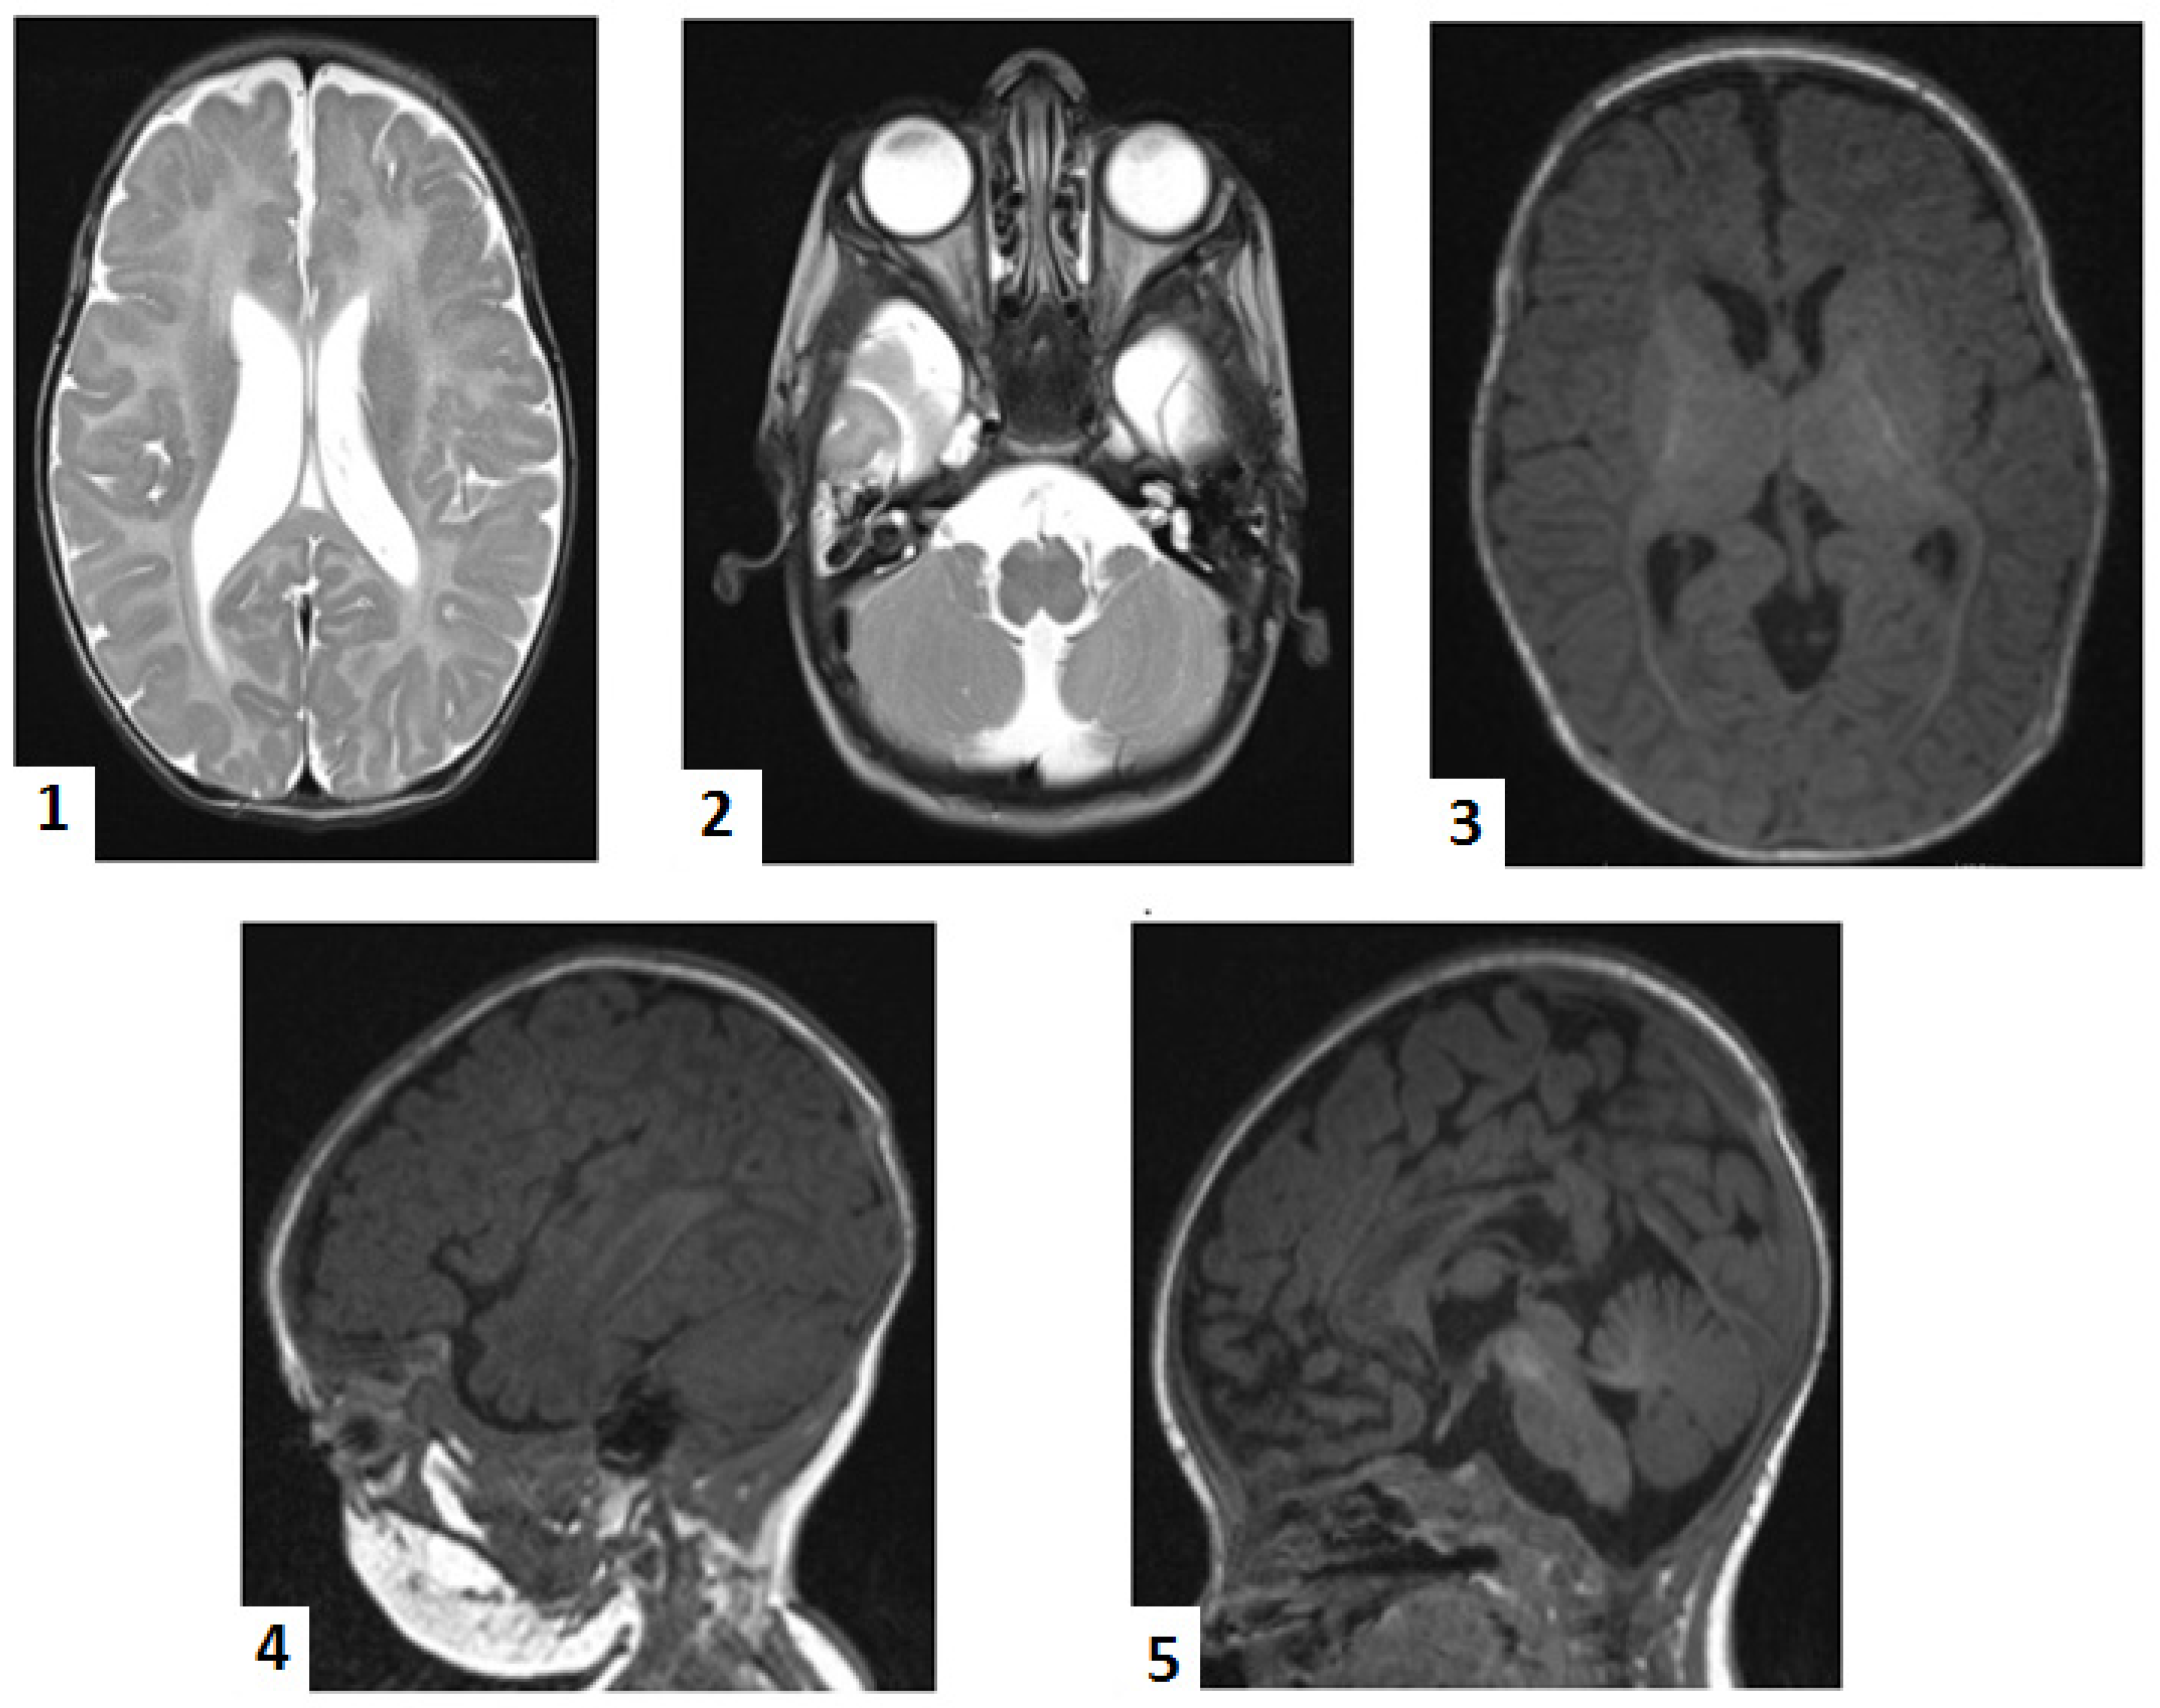

The infant had an unfavorable clinical course, with recurrent respiratory tract infections leading to multiple hospital admissions and outpatient evaluations (Figure 2). The anticonvulsants’ dosages had to be adjusted several times. Hypotonia, hyporeflexia, and absent osteotendinous reflexes persisted over time. Feeding difficulties led to protein-caloric malnutrition and anemia despite high-calorie feedings and vitamin and iron supplementations. At 8 months, the infant’s developmental quotient was equivalent to a one-month-old’s. She had no control, limited fine and gross motor ability (hardly grasping and manipulating objects), nonverbal communication, and severely delayed impressive and expressive language. The infant demonstrated a weak cry, affective immaturity, and fluctuant behavior.

The infant presented various types of seizures almost daily, which required continuous adjustments of anticonvulsants doses and regimens. Following the neonatal period, the seizures predominantly became focal, initially every 2–3 days, increasing in frequency towards one year of age, when, despite treatment, occurred daily, associated with apnea. Conventional electroencephalography, performed in time, showed a disorganized pattern with a 2–3 Hz delta rhythm, variable amplitude (12–40 µV), and overlapping sharp-wave and polysharp-wave bilateral discharges, particularly in frontal and temporal derivations from various foci. Abdominal ultrasound performed at 8 months revealed bilateral hydronephrosis grade II. A sudden increase in the cranial circumference associated with sleepiness prompted the parents to seek an outpatient evaluation. The cranial computer tomography (CT) performed at this moment confirmed the ultrasound aspect of mixed-obstructive and secondary to white matter loss—hydrocephalus with periventricular edema. Callosal dysgenesis and megacisterna magna were also observed. The infant underwent ventriculoperitoneal shunting, which was uneventful. There was a short-term improvement in the neurological status, but the next day, almost continuous seizure activity imposed invasive ventilation. Recurrent bradycardia and asystole followed, and despite inotropic, vasoactive support and extensive resuscitation maneuvers, the infant passed away a few hours later.

Figure 2. Clinical course, investigations, and follow-up of the proband. Legend: m—months; d.—days; R—outpatient re-evaluation; DOL—day of life; HUS—head ultrasonography; US—ultrasonography; MLPA—multiplex ligation-dependent probe amplification; SMA—spinal muscular atrophy; MRI—magnetic resonance imaging; WES—whole exome sequencing; CT—computer tomography.